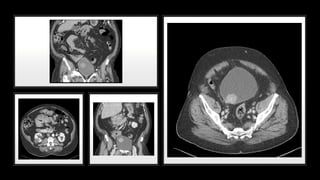

• #46 EXTRA PERITONEAL Mechanism of injury Shearing or direct laceration CT Cystography Flame shaped Extravasation of contrast into perivesical soft tissues Treatment Conservative: bladder catheter drainage (superpubic and transurethral)

• #47 INTRA PERITONEAL Mechanism of injury Blunt trauma CT Cystography Extravasation of contrast around bowel loops and in paracolic gutters Treatment Aggressive: Prompt open surgical exploration (because risk of urinary peritonitis)